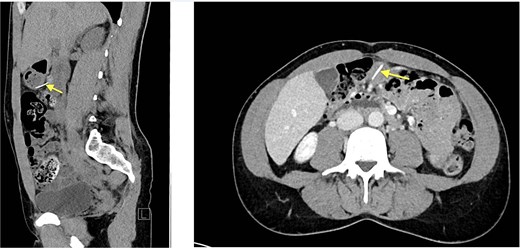

Four months later, a 33-year-old man presented with fever and weakness of unknown origin for 5 days. He was barbecuing a lot in the last weeks, as he was on vacation. Epigastric tenderness was present at admission. Laboratory parameters showed elevated inflammatory markers. CT scan (Fig. 3) showed a liver abscess with a metal foreign body.